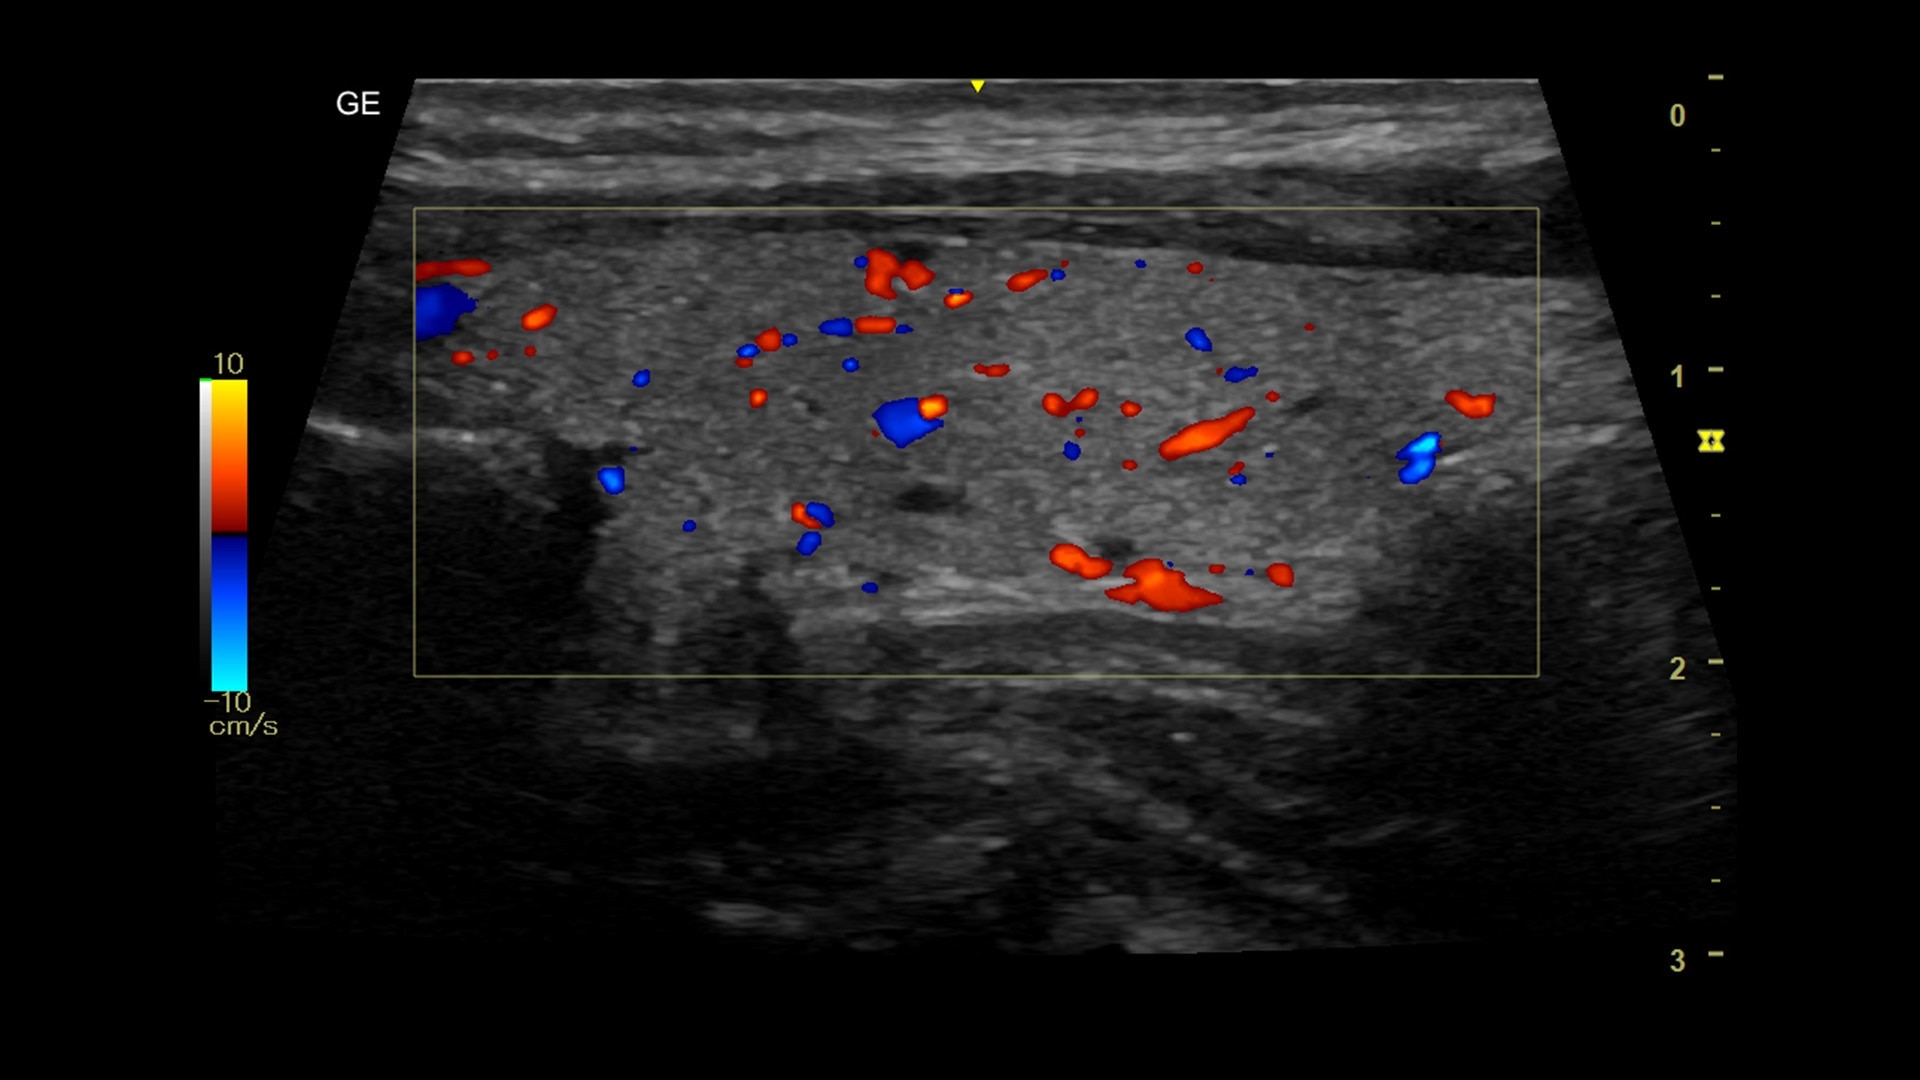

Efficient

Simple-to-use design, workflow and automated tools streamline workflow